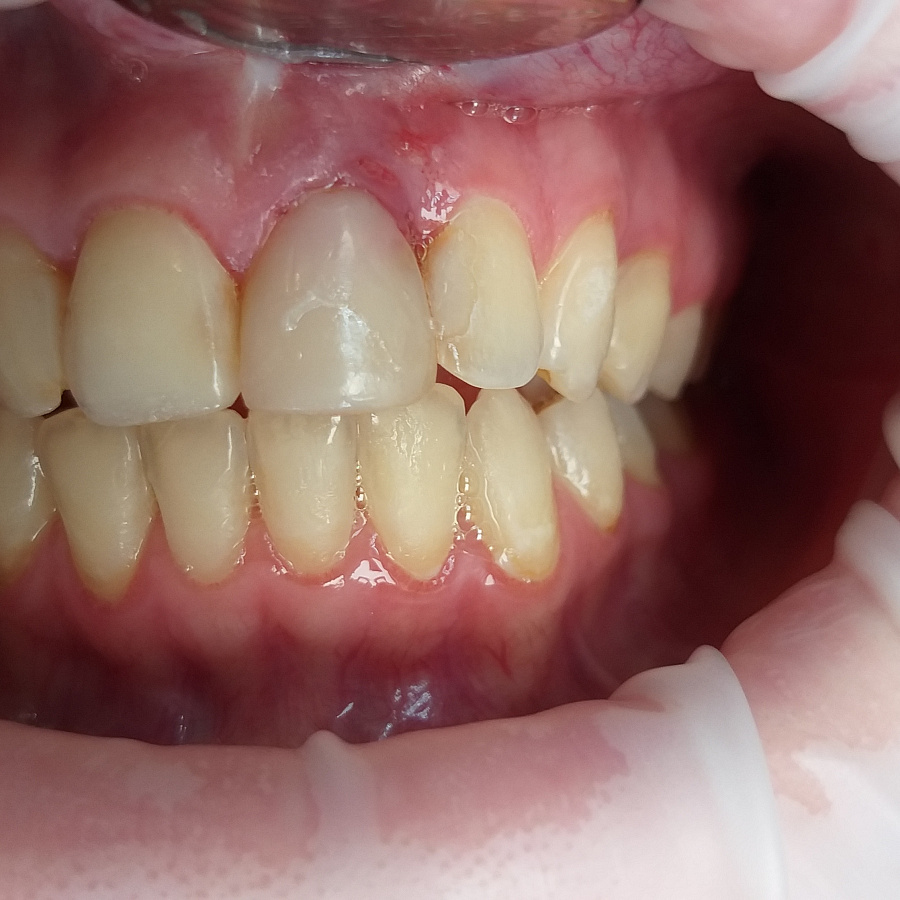

Пациентка обратилась в клинику с жалобами на воспаление десны в области переднего зуба верхней челюсти, необычный вид десны, кровоточивость десны во время чистки зубов.

Поставлен диагноз посттравматическая резорбция корня.